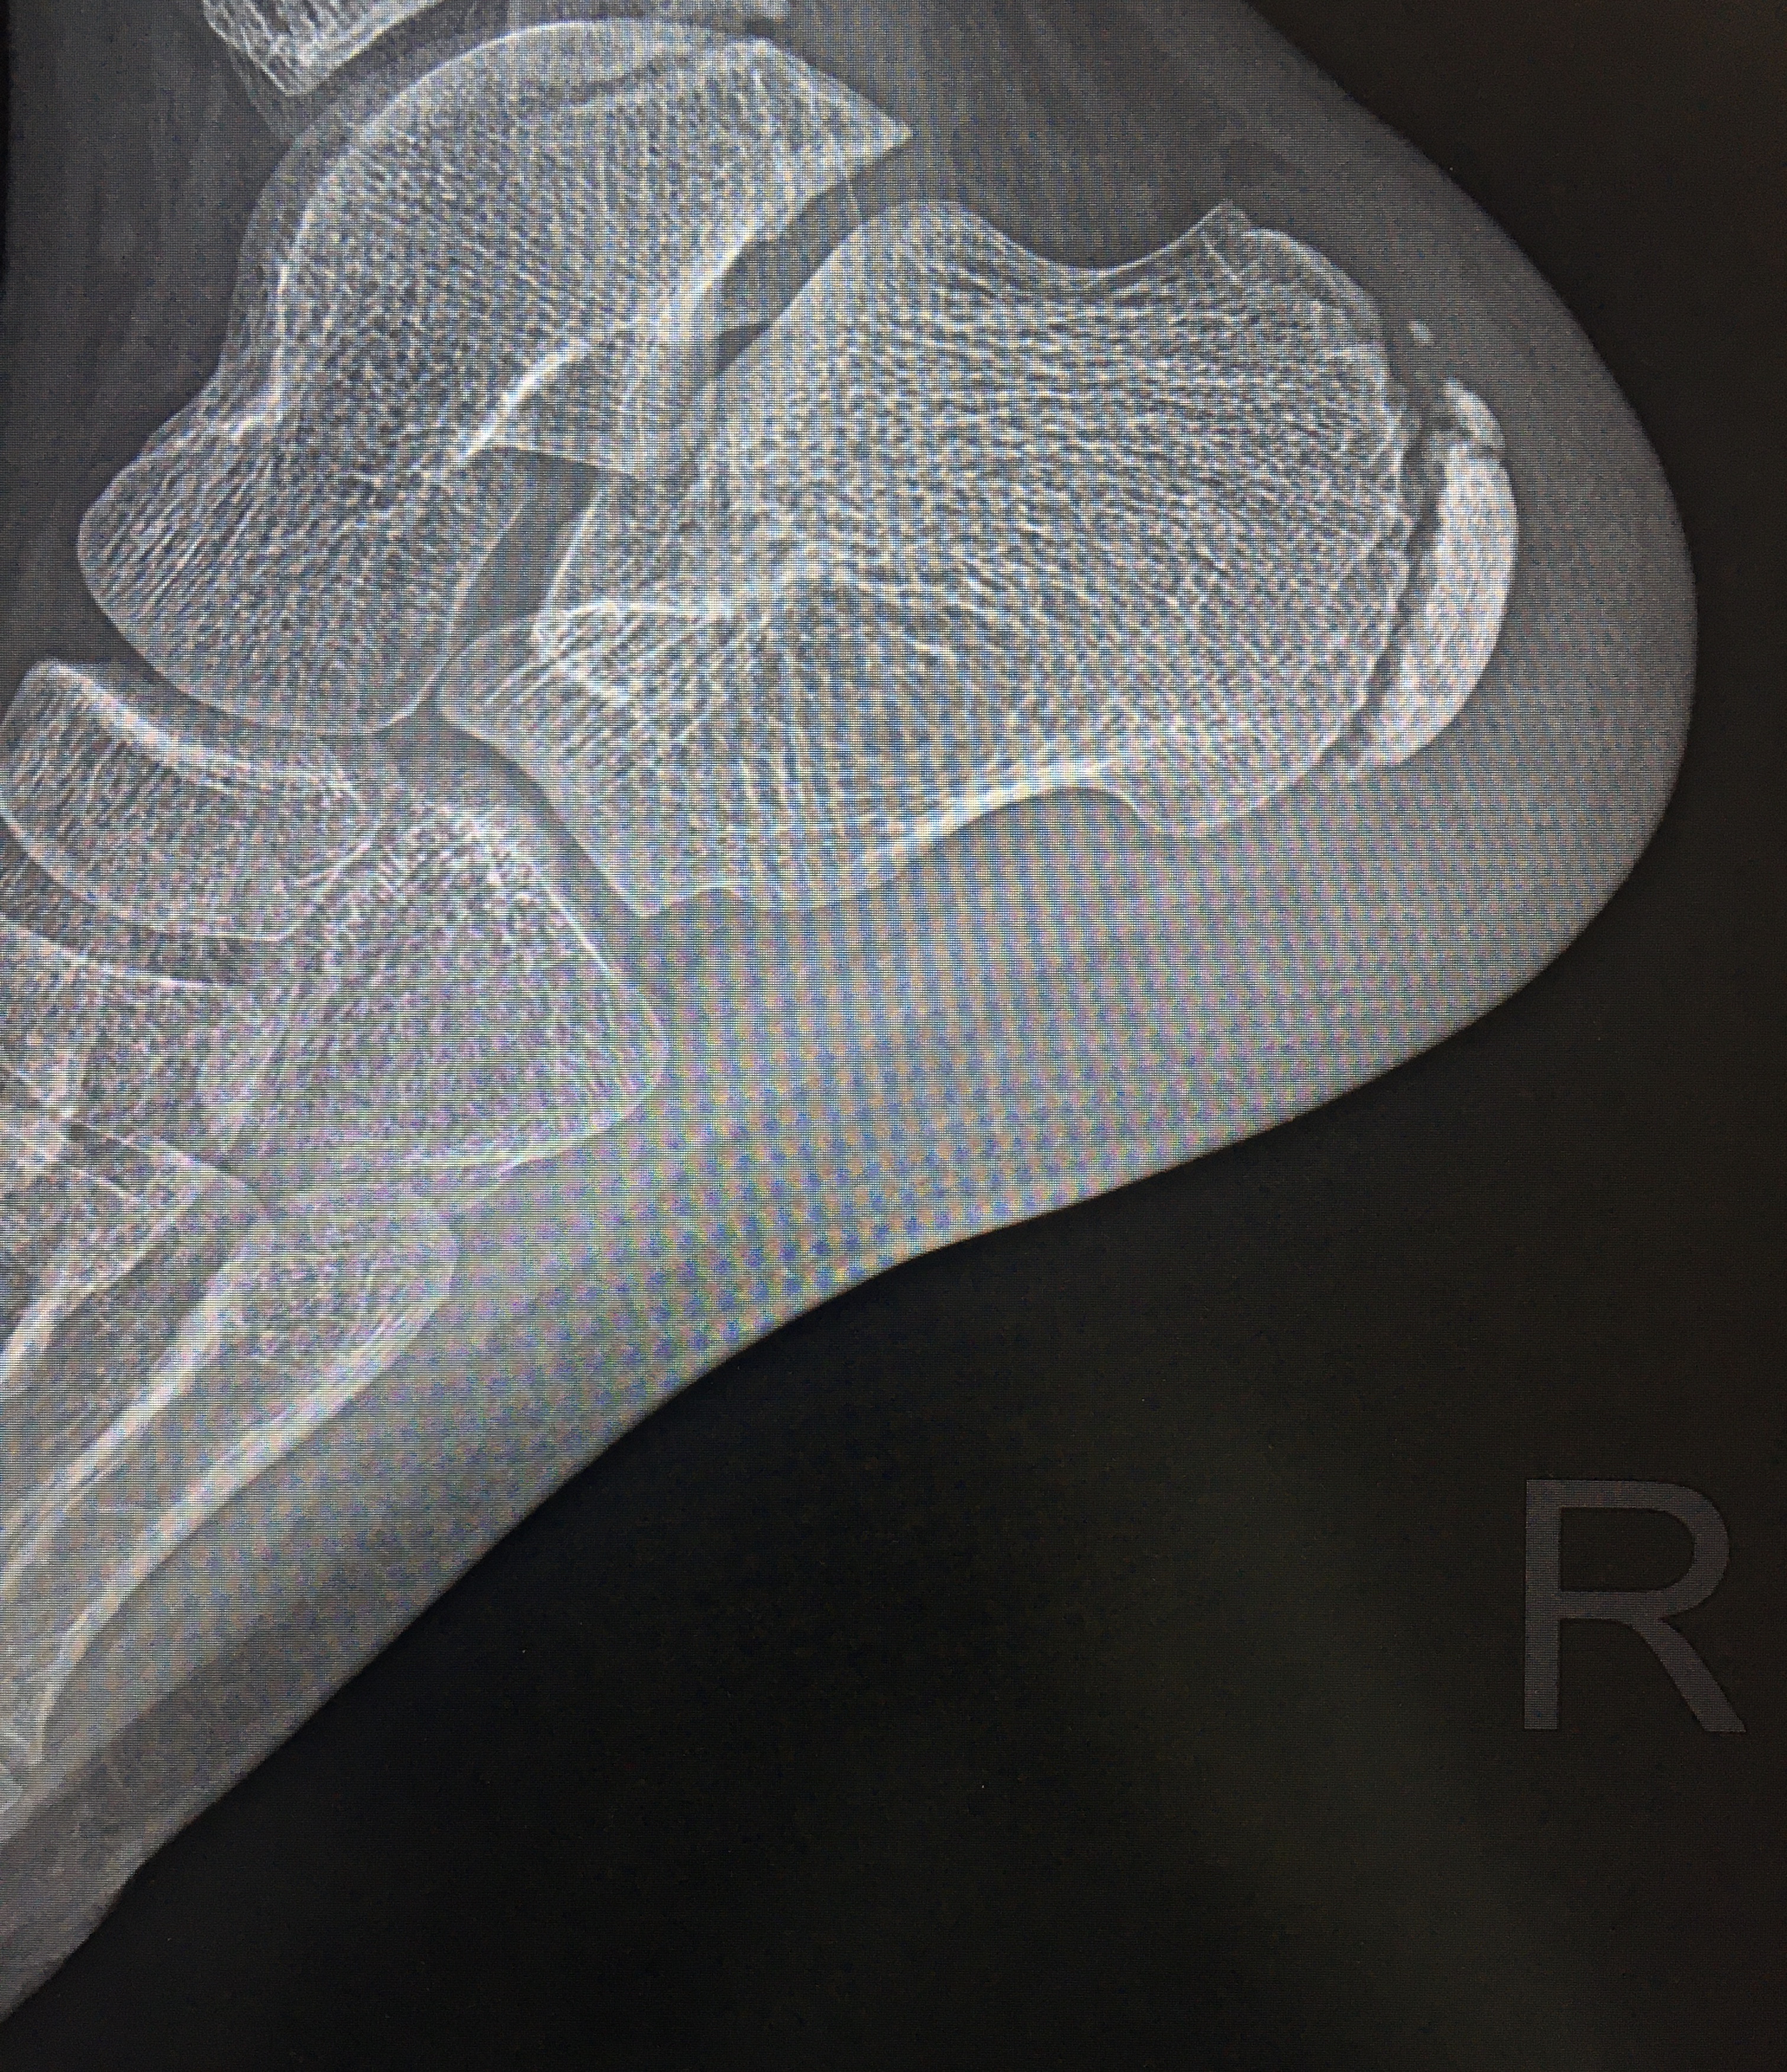

Возраст 12 лет . До сих пор не могу понять , когда точно можно утверждать о болезни Хаглунда-Шинца . Кто-то при виде фрагментации апофиза пяточной кости сразу пишет про это , а кто-то считает нормой...

13. Болезнь Шинца?

Мальчик, 2011 года. Пациента не видела. В направлении не очень поняла что написано, но вроде болезнь Хаглунда справа. Если я правильно помню, то хаглунда это деформация пяточного бугра, у детей...

Добрый день! У ребенка стали болеть пятки, но только во время прыжков. Даже при ходьбе не болять, но во время прыжков на батуте болят сильно по ее словам. Дочке 11 лет. Ортопед сказал, что на ренгене...